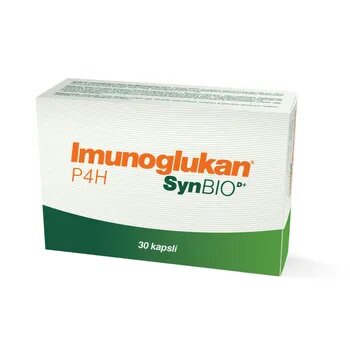

Vitamins & Supplements